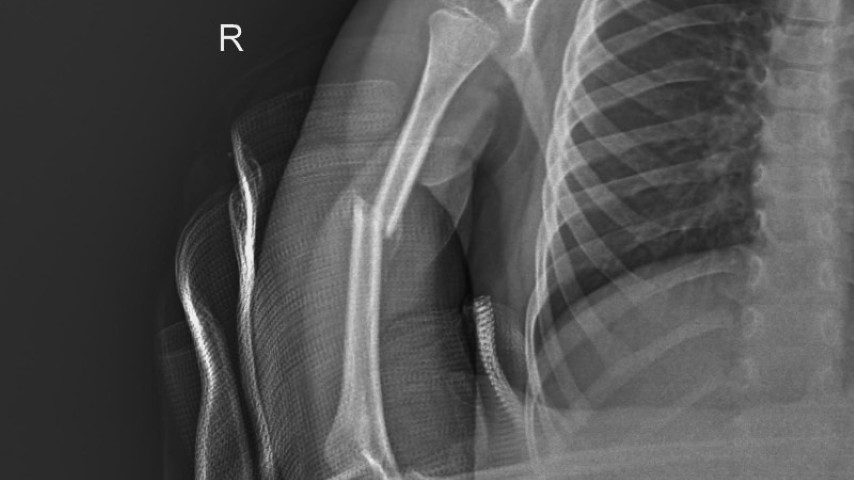

Denuncian omisión para responder por lesiones de alumno

Un menor de 5 años de edad, fue operado 20 días después de una fractura de húmero, luego de que un compañero de necesidades especiales del Preescolar María Enriqueta Camarillo, ubicado en San ...